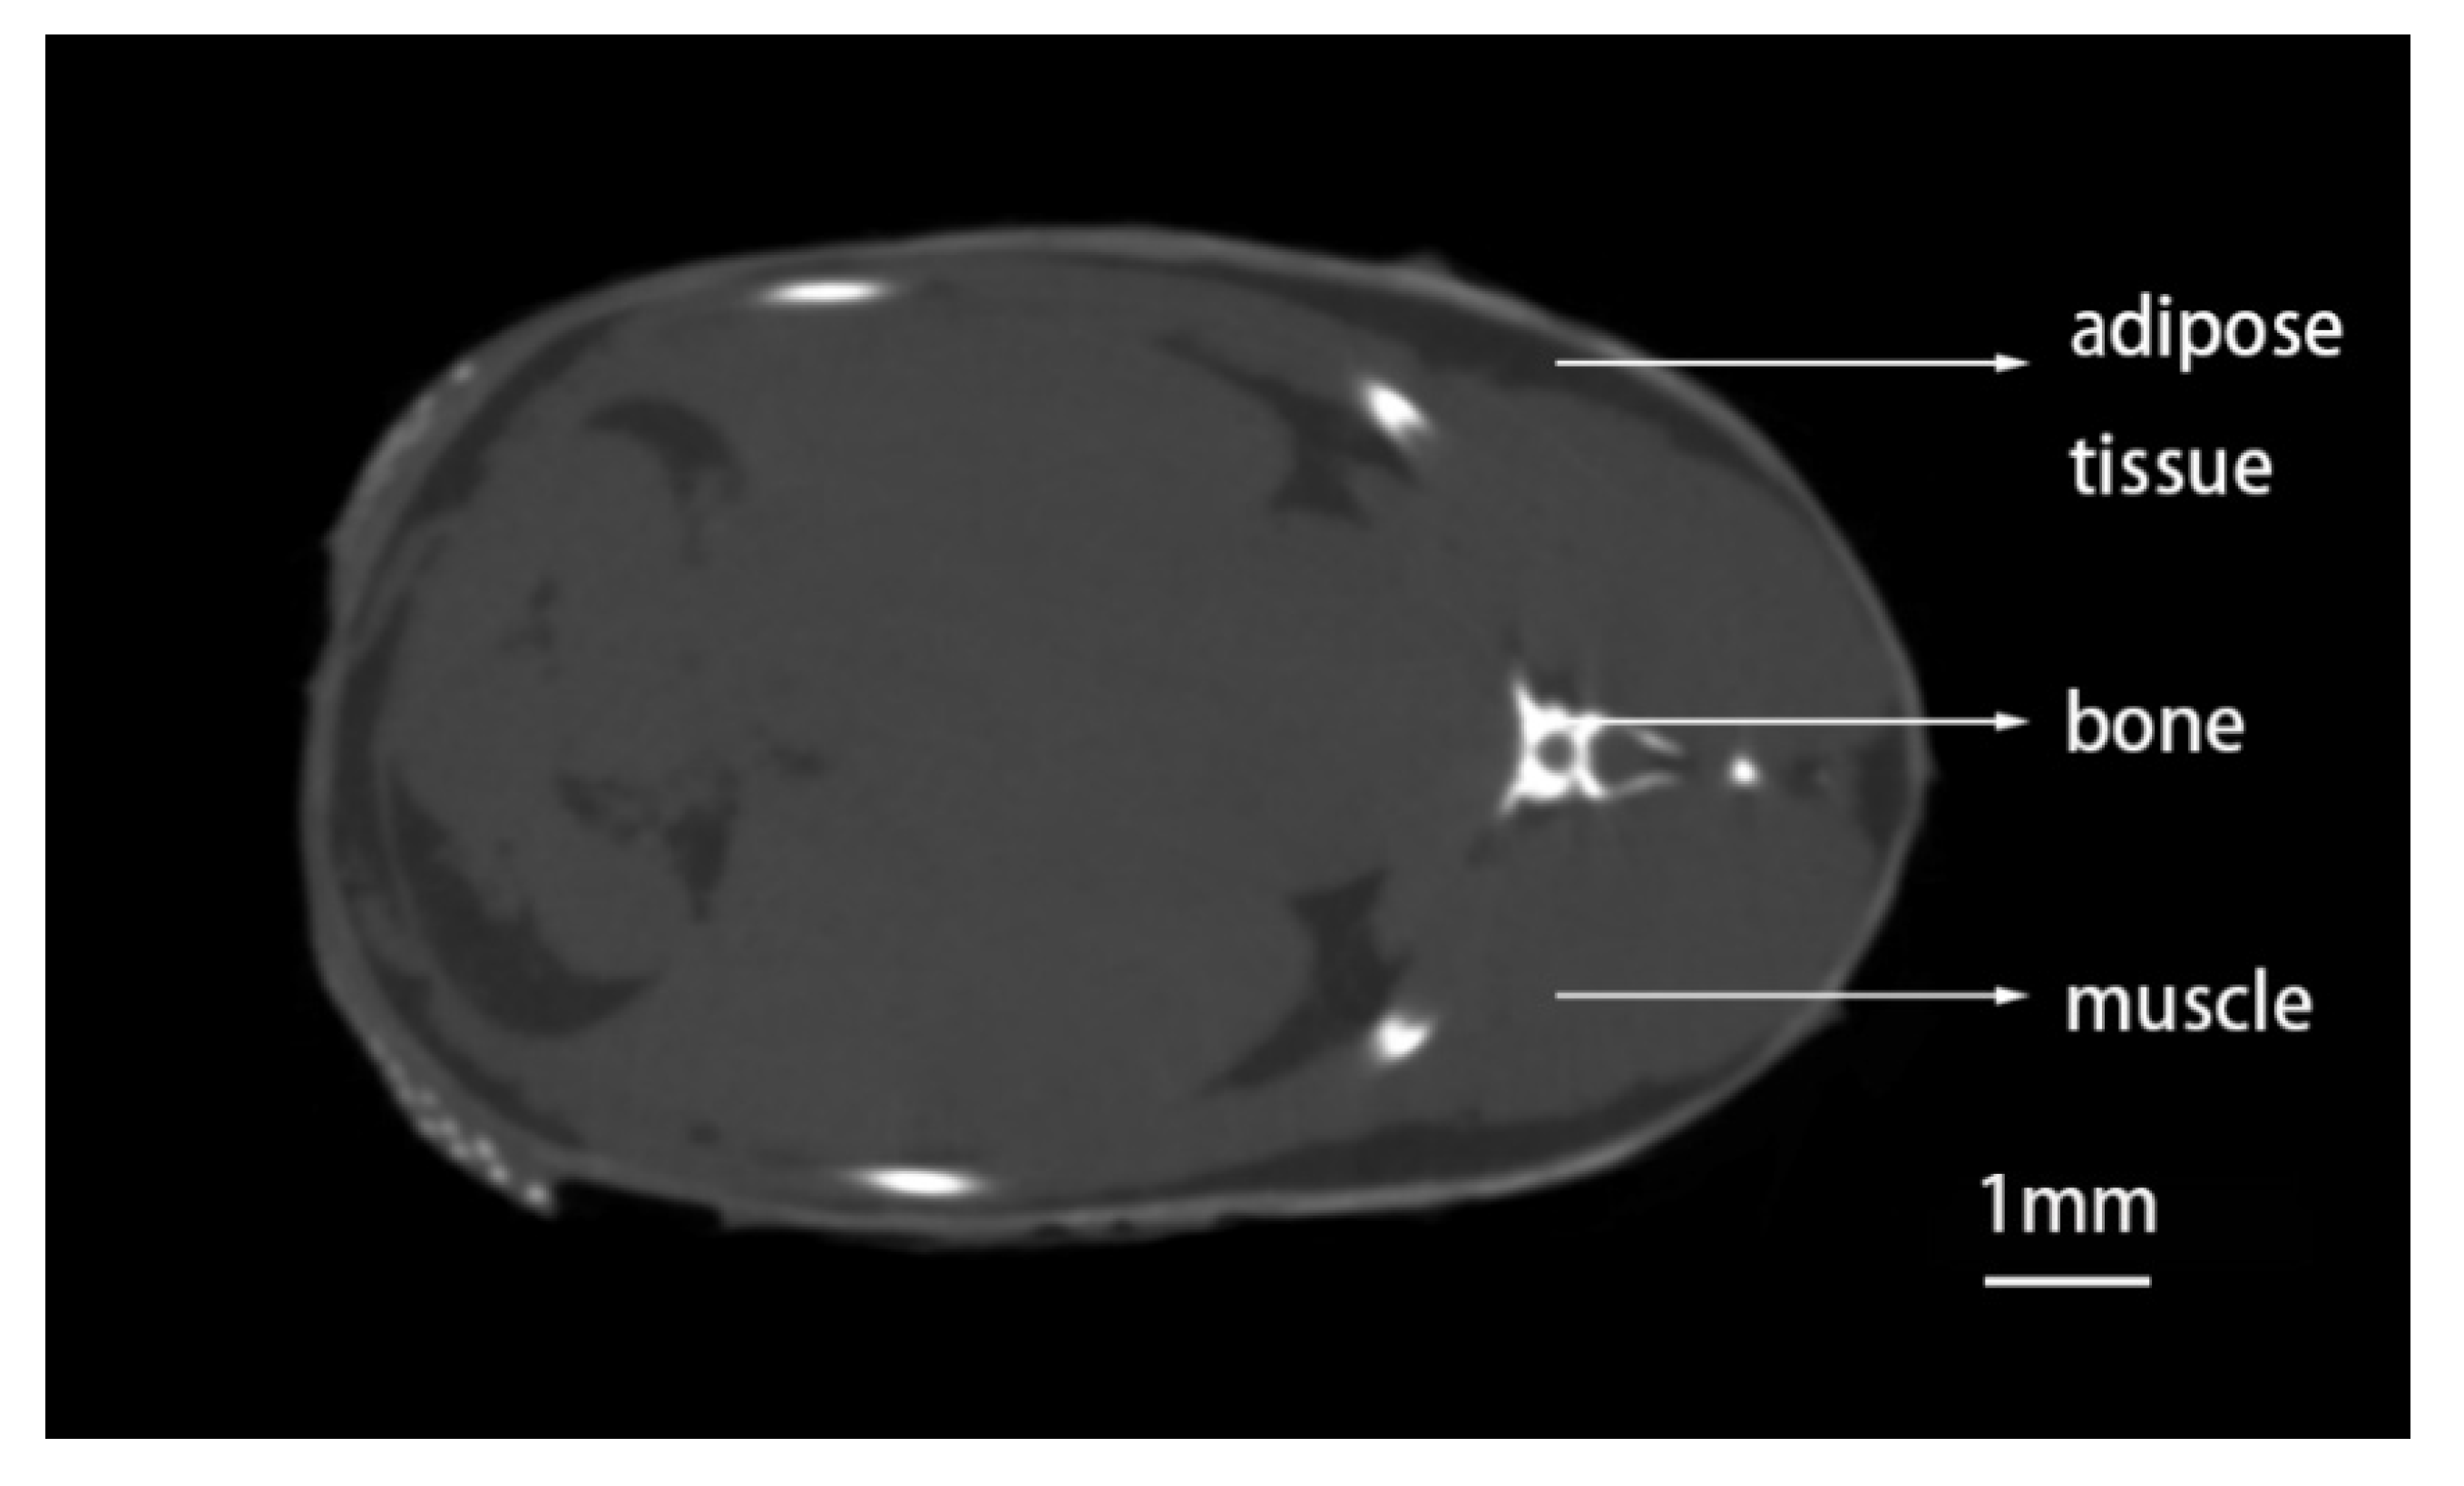

3.1. Method to Detect Adipose Tissue in Zebrafish by CT Scanning

3.2. Distribution of Adipose Tissue in Zebrafish